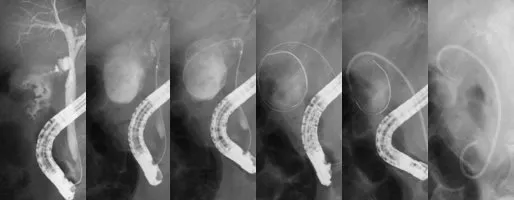

内視鏡的胆嚢ドレナージ術(ETGBS)【下図】

急性胆嚢炎に対する内視鏡的胆嚢ドレナージ術(ETGBS)による治療。 高齢のため胆嚢摘出術が困難な症例、あるいは手術までの待機的治療としても有効である。 - 内視鏡的経鼻胆管ドレナージ術(ENBD)